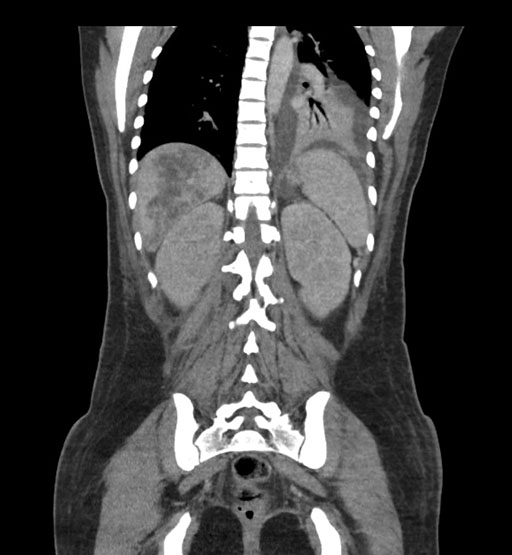

Axial Arterial

Coronal Arterial